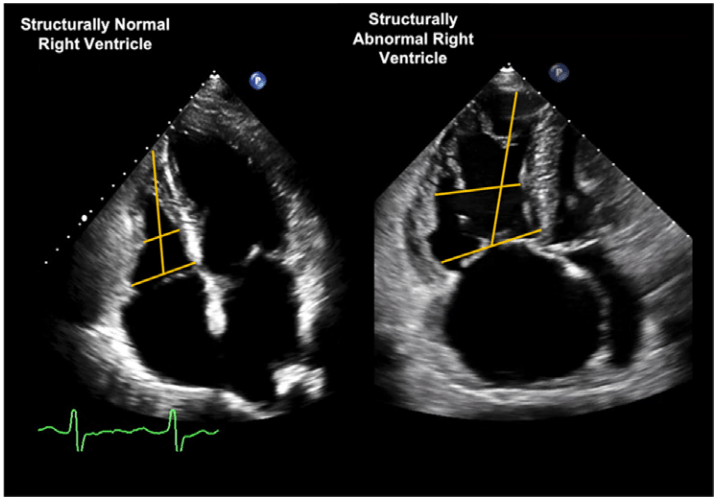

According to ASE, the view we should measure the RV size dimensions in the apical 4

RV-focused apical 4-chamber view

Cutoffs for RV size measurement according to ASE

41 - 35 - 83